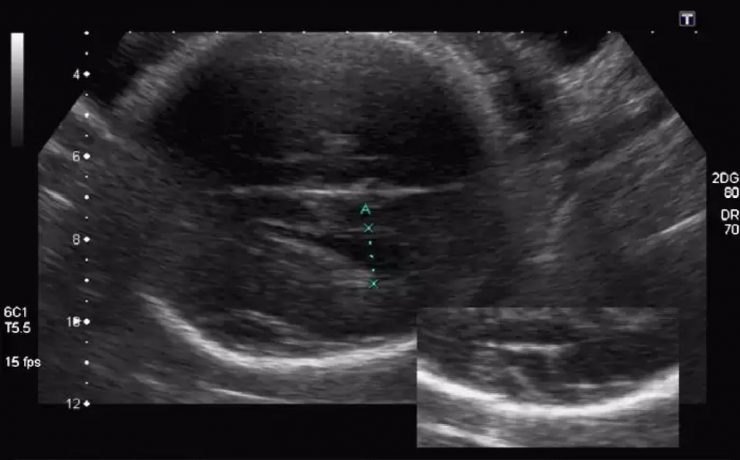

Signo radiológico: “el lirio caído”

El signo del lirio caído , fue descrito hace más de 40 años en pielografía de eliminación y corresponde al aspecto que adquiere el sistema pieloureteral inferior en un riñón con doble sistema excretor, dado por una pelvis renal de orientación horizontal y cálices que se dirigen discretamente hacia cauda.